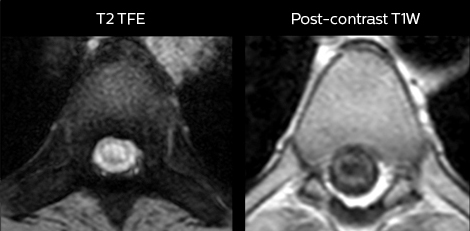

in image acquisition and postprocessing algorithms.”“mDIXON TSE sequences allow simultaneous characterization of morphological changes from the in-phase T2-weighted images and visualization of edematous changes, thanks to the water T2-weighted images from the same acquisition. Anatomical and morphological considerations could be a partial or complete ligament tear, a bony avulsion or hematoma.” “For soft tissue assessment mDIXON brings similar benefits. For example in one T2-weighted mDIXON TSE acquisition, having the multiple contrasts helps us assess abnormalities in peripheral nerves fascicles, which may be due to anatomical or inflammatory changes..” “In peripheral joints, we get good image quality in difficult areas with mDIXON TSE. Fat suppressed images appear homogeneous over the entire image, even with large coverage at 3.0T – for instance in scapular or hip girdles – or in the bearing areas or around metal prostheses*, where fat suppression is often deficient with STIR or spectral fat suppression, causing diagnostic difficulties. If a diagnostic image is right the first time, we don’t need to repeat or add a sequence.” “mDIXON TSE sequences allow simultaneous characterization of morphological changes from the in-phase T2-weighted images and visualization of edematous changes, thanks to the water T2-weighted images from the same acquisition. Anatomical and morphological considerations could be a partial or complete ligament tear, a bony avulsion or hematoma.” “For soft tissue assessment mDIXON brings similar benefits. For example in one T2-weighted mDIXON TSE acquisition, having the multiple contrasts helps us assess abnormalities in peripheral nerves fascicles, which may be due to anatomical or inflammatory changes..”